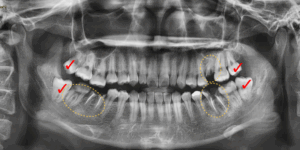

전체적인 치열이 고르지 않은 상황이었고

상하좌우 4개의 매복사랑니가 있었으며

군데군데 이미 충치가 깊어서 뿌리만

남아있는 치아가 여러개 있었습니다.